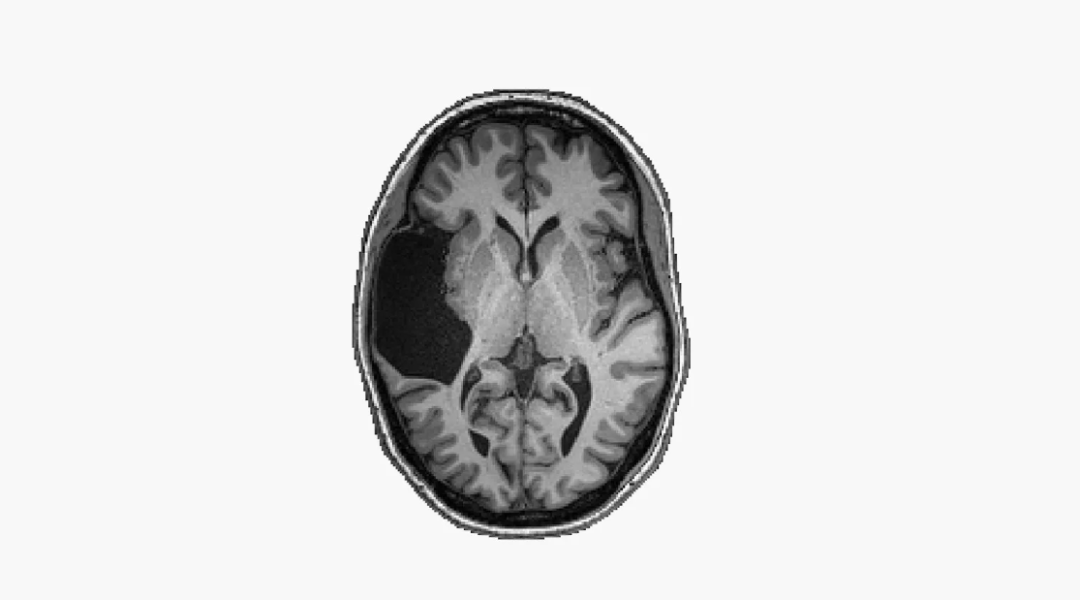

EG大脑的一幅核磁共振影像

EVELINA FEDORENKO, GRETA TUCKUTE/BRAIN AND COGNITIVE SCIENCES